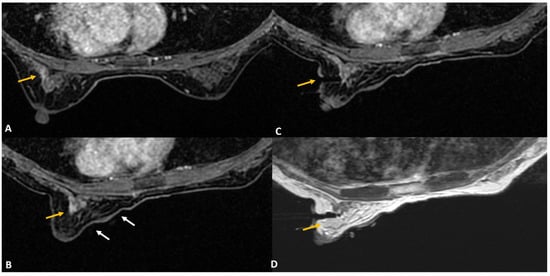

Figure 4.

(A). In a woman with newly diagnosed left breast cancer, staging MRI identified a 6 mm indeterminate enhancing mass (yellow arrow) in the right breast located posteriorly close to chest wall. (B). During biopsy small dead space (red asterisks) is always noted close to the chest wall that lies beyond the grid. (C). For biopsy, the introducer was inserted through the posterior most hole in the grid (blue arrow) close to the lesion (yellow arrow). The needle failed to reach the target adequately. A second introducer guide was inserted outside the grid (in the area of red asterisks), close to the chest wall using free-hand direct puncture. (D). The posterior needle (red arrow) was seen to adequately reach the target and biopsy was completed successfully. The histology was reported as lobular neoplasia.